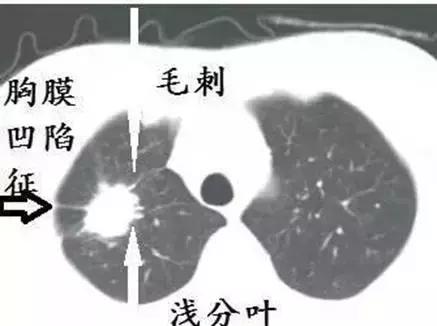

有些恶性肺小结节会表现出一些典型的影像学特征,比如:结节内有空泡或空洞、有支气管、血管通过、分叶、边缘有毛刺、牵拉周围胸膜等。

这是因为恶性肿瘤会“疯长”,很有侵略性,往四周扩散很快,所以出现张牙舞爪的“毛刺”,由于长得太快,肿瘤中间的细胞得不到足够的养分,就会饿死,从而出现坏死,而出现“空洞”。